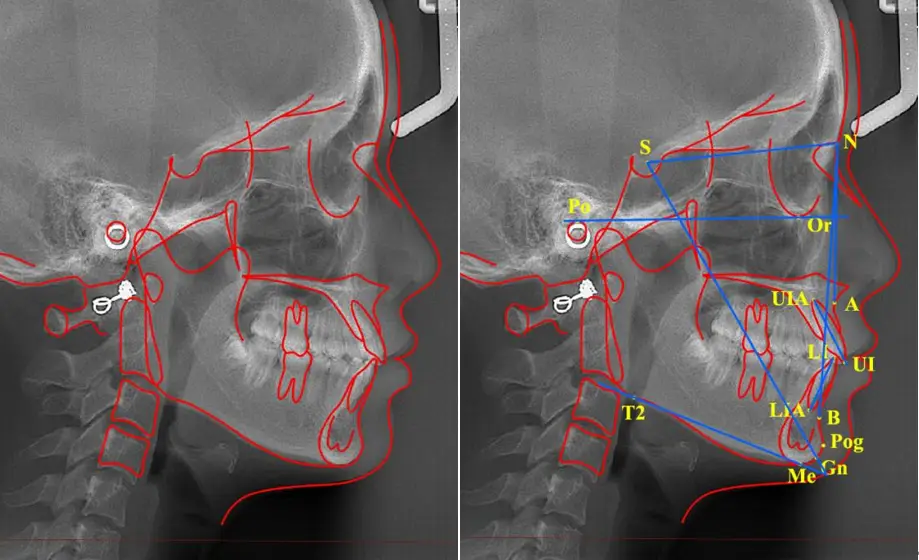

AI头影测量分析功能上线!

AI头影测量分析功能上线!按病例收费,每个病例付费分析一次生成数据之后,可以随时查看。